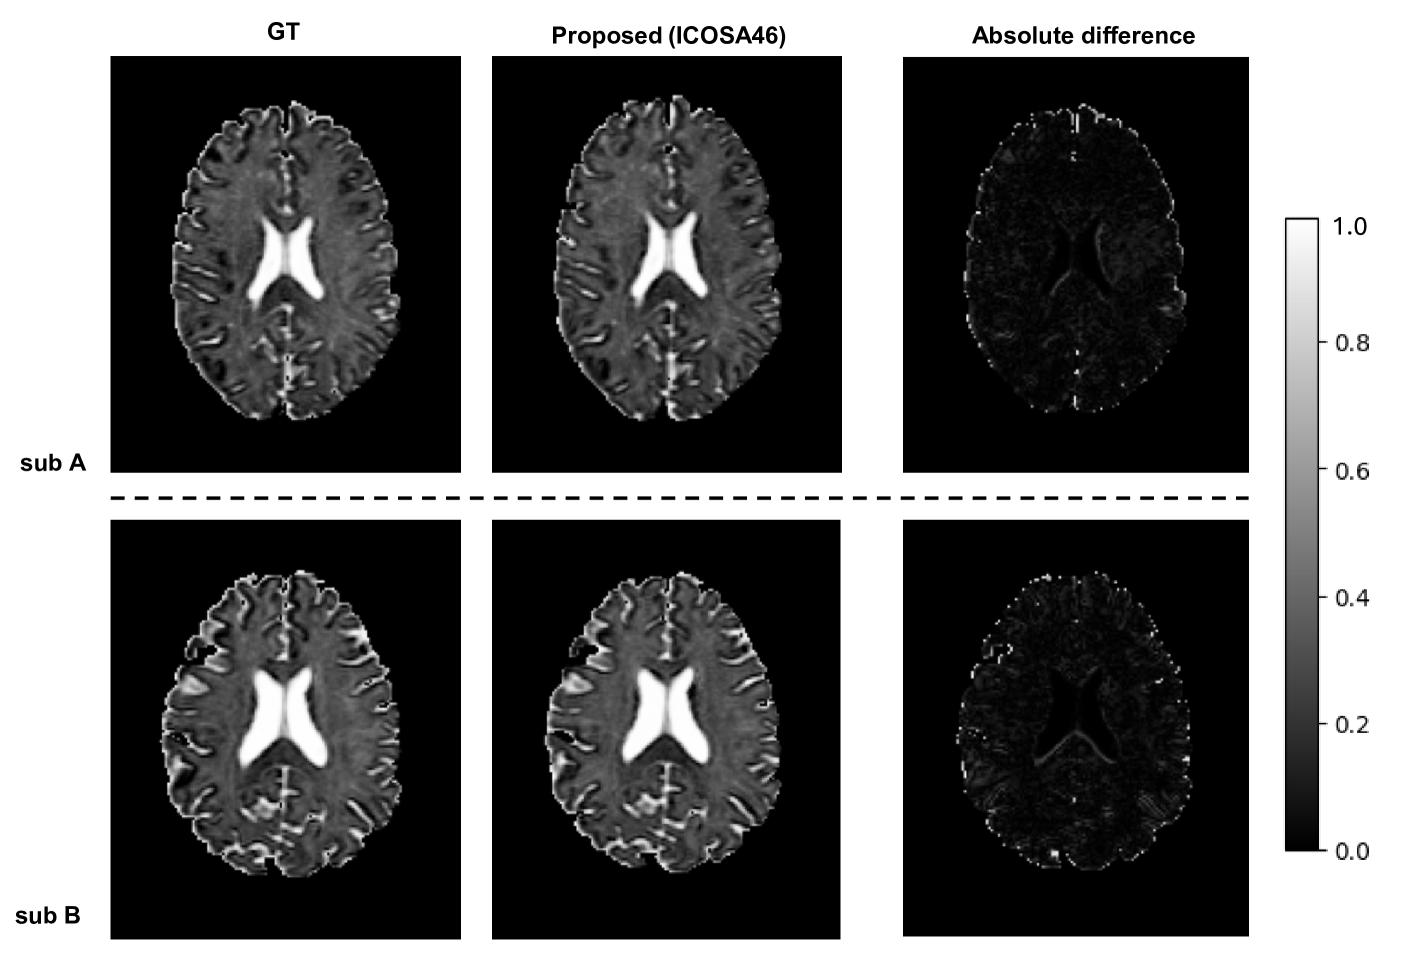

Refer to caption

Figure 4: Qualitative Result. Two subjects from the test cohort are visualized for assessment of free water estimation.

The proposed Polyhedra Encoding Transformer models, utilizing different levels of icosahedral resampling (ICOSA6, ICOSA21, and ICOSA46), further enhanced performance as compared with the basic transformer, particularly with higher levels of tessellation and resampling. The ICOSA46 variant consistently achieved the best results, with the lowest RMSE values for FWF estimation (e.g., 1.421 E-04 for HCP) and the highest ACC values for SHC (e.g., 0.835 for HCP). The ICOSA21 model also performed robustly, frequently placing in the top two across most metrics and datasets, indicating that higher levels of icosahedral resampling contribute positively to both anisotropic and isotropic feature learning. However, the ICOSA6 variant did not perform as well as the higher-resolution icosahedral configurations. This is likely due to the lower resolution of the q-space sampling inherent in ICOSA6, which consists of only 20 directions. The reduced resolution may not adequately capture the full complexity of the diffusion signals, leading to less accurate feature representation.